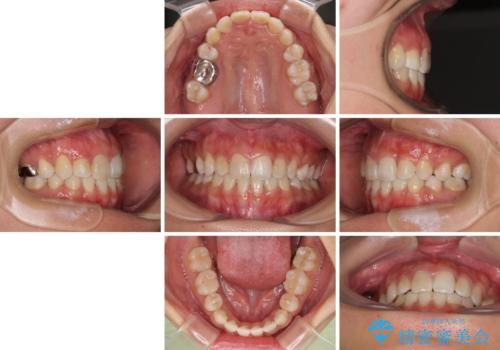

裏側装置での矯正治療は、上顎前歯の正中のズレをまっすぐに改善することが難しいのですが、きれいに整えることができました。

補助装置を用いて抜歯したスペースを速やかに閉じたことで、短期間での治療となりました。